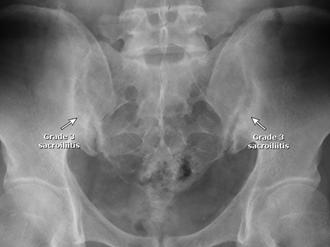

♦ Sacroileítis en la radiografía (grado 2 bilateral o grado 3-4 unilateral) o resonancia magnética (edema de médula ósea u osteítis) más ≥ 1 característica de espondiloartritis a continuación, O

Figura 14. Sacroileitis

Radiografías simples de la columna y la pelvis como técnicas de imagen iniciales